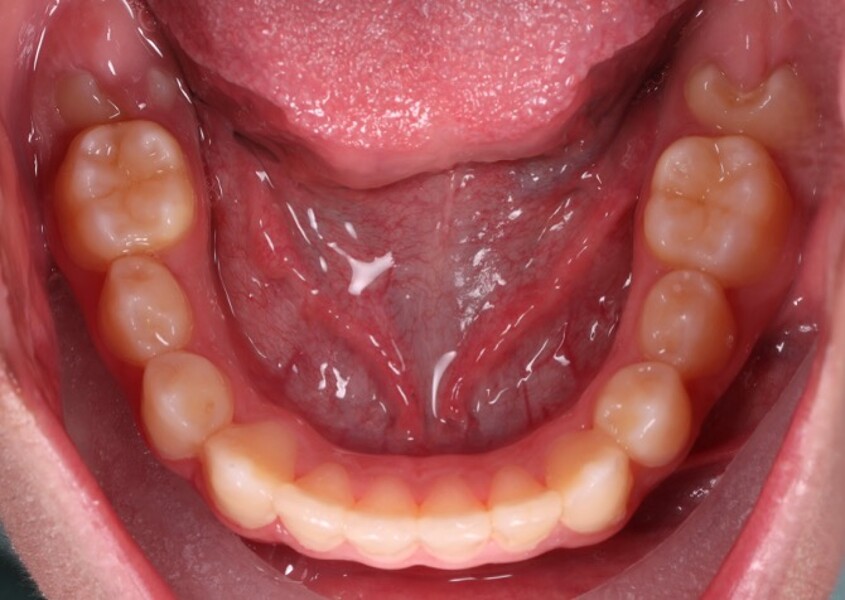

Figs. 6a–e: Intra-oral photographs after the first phase of treatment.

Fig. 6b

Fig. 6c

Fig. 6d

Fig. 6e

At the end of the first phase of treatment, the clinical findings included (Figs. 5 & 6):

Class I molar and canine relationships on the left side;

half-cusp Class II relationships on the right side;

normal overjet (2.0 mm) and overbite (2.5 mm); and

a posterior open bite, particularly on the left side.

Cephalometric analysis showed that the sagittal discrepancy had been significantly reduced (ANB = 3.7°; Wits = 1.8 mm). Mandibular length remained below normative values.